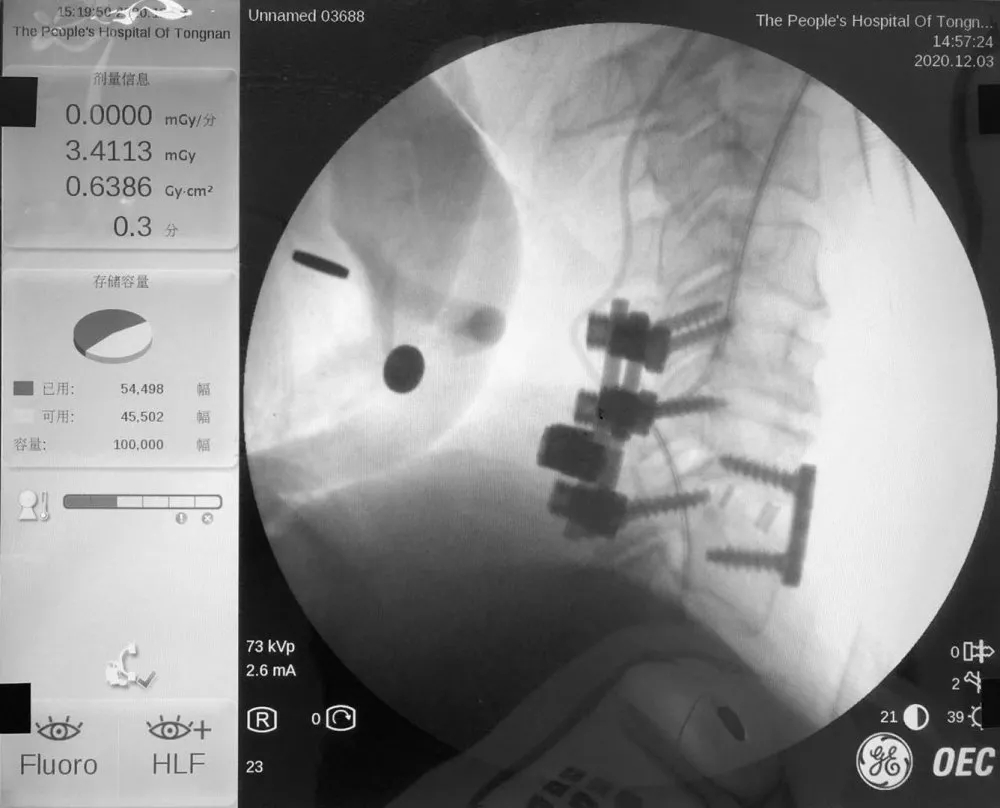

为确保手术顺利开展,科室团队反复斟酌、制订手术方案后,在院本部脊柱外科郝杰教授的指导下,进行了“经颈椎后路椎管减压+颈5.6.7椎体侧块螺钉融合固定+经前路颈5.6椎间盘摘除、椎管减压、椎间植骨融合、内固定”手术。经过近5个小时手术,患者手术顺利,术后病情无反复,持续治疗中。

术后